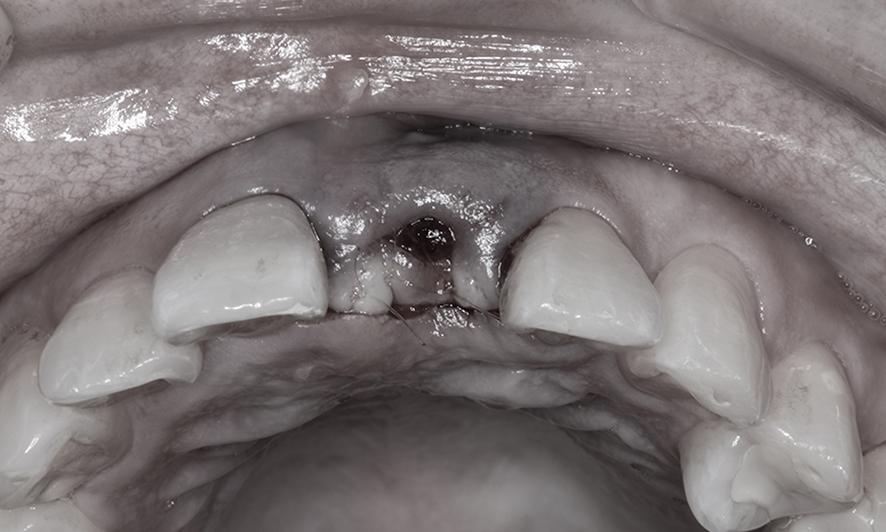

CTスキャンを用いて骨と歯肉の状態を精査したところ、骨の厚さはインプラントに適しているものの、歯ぐきの高さが不足していることが判明しました。そこで、インプラント手術と同時に「結合組織移植術(CTG)」を行い、歯ぐきの高さと厚みを補う計画をご提案しました。

手術では、事前シミュレーションで決定した理想的な位置にインプラントを埋入するため、「埋入ガイド(ステント)」を用いて精密に処置を行いました。さらに、歯ぐきを慎重に剥離し、必要な厚さを盛り足して縫合しました。

CT画像から歯ぐきの垂直的な厚みが足りないことが確認できた

インプラント埋入と同時に結合組織移植術のために、部分層弁という手法で一部の歯茎を慎重に剥がします。

初診時の歯ぐきの状態。ちょうどよく見えるがこのまま埋入すると審美審美性が損なわれてしまう。